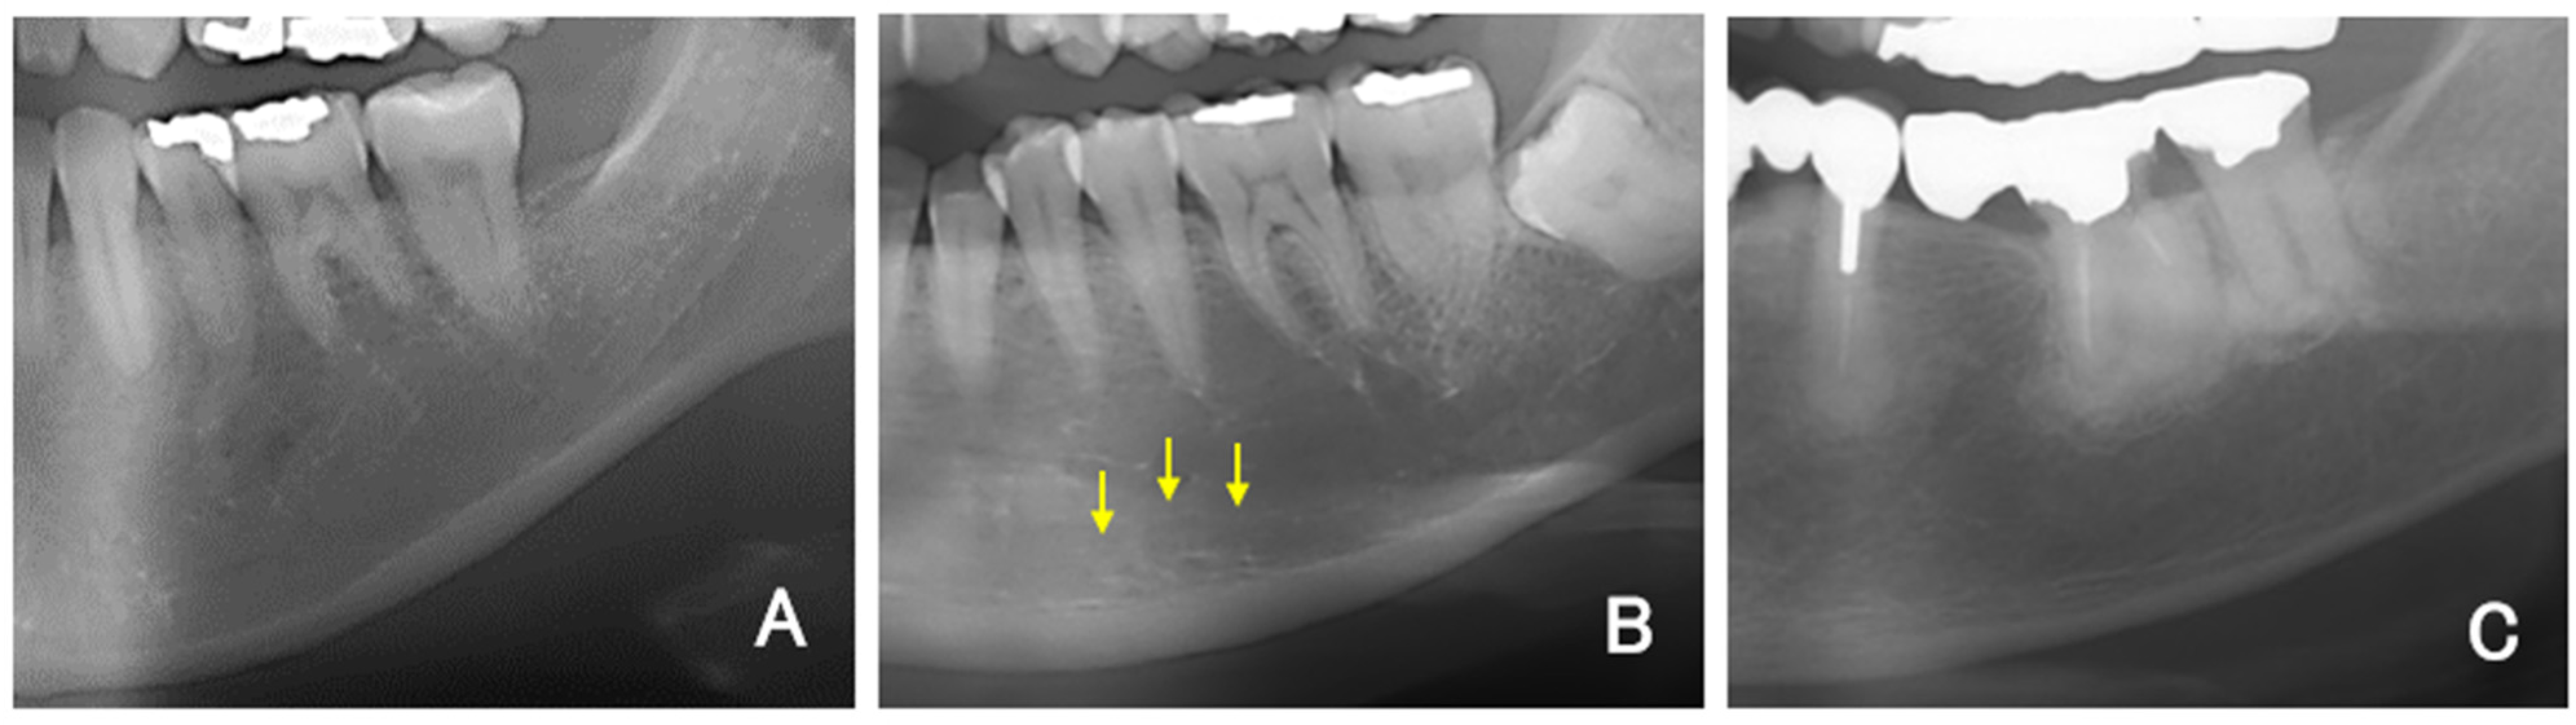

For all DPR images, the mandibular inferior cortical bone morphology was classified into three types according to a report by Klemetti and Kolmakow [20]. Class 1 (C1) has a smooth inner surface of cortical bone, class 2 (C2) has an irregular inner surface of cortical bone with linear resorption, and class 3 (C3) has severe linear resorption and cortical bone rupture over the entire cortical bone (Figure 1A–C). Diffuse opacities, such as sclerosing osteomyelitis that did not correspond to any of the above types, were recorded separately. Two sites on the left and right sides were evaluated and recorded per patient. Therefore, 140 sites were covered in the DPR images. The MCI was assessed twice by dentists (K.S., a periodontist; T.Y., an oral surgeon; and Y.A., a dental trainee) who had been trained in classification, and the second assessment was used. The classification result was replaced with a numerical value, such as 1 for C1, 2 for C2, and 3 for C3, and the averages of the three examiners’ values were rounded to obtain the final MCI (e.g., if the mean value was 1.66, then it was classified as C2). The interindividual reproducibility (kappa coefficient) was examined for the three dentists who made the evaluations in this study. Tests were conducted in combinations of two dentists each (K.S. and T.Y., T.Y. and Y.A., Y.A. and K.S.).

Figure 1.

(A) Representative example of C1. (B) Representative example of C2. Multiple upper marginal lines of the mandibular inferior cortical bone were identified and obscured (arrows). (C) Representative example of C3.